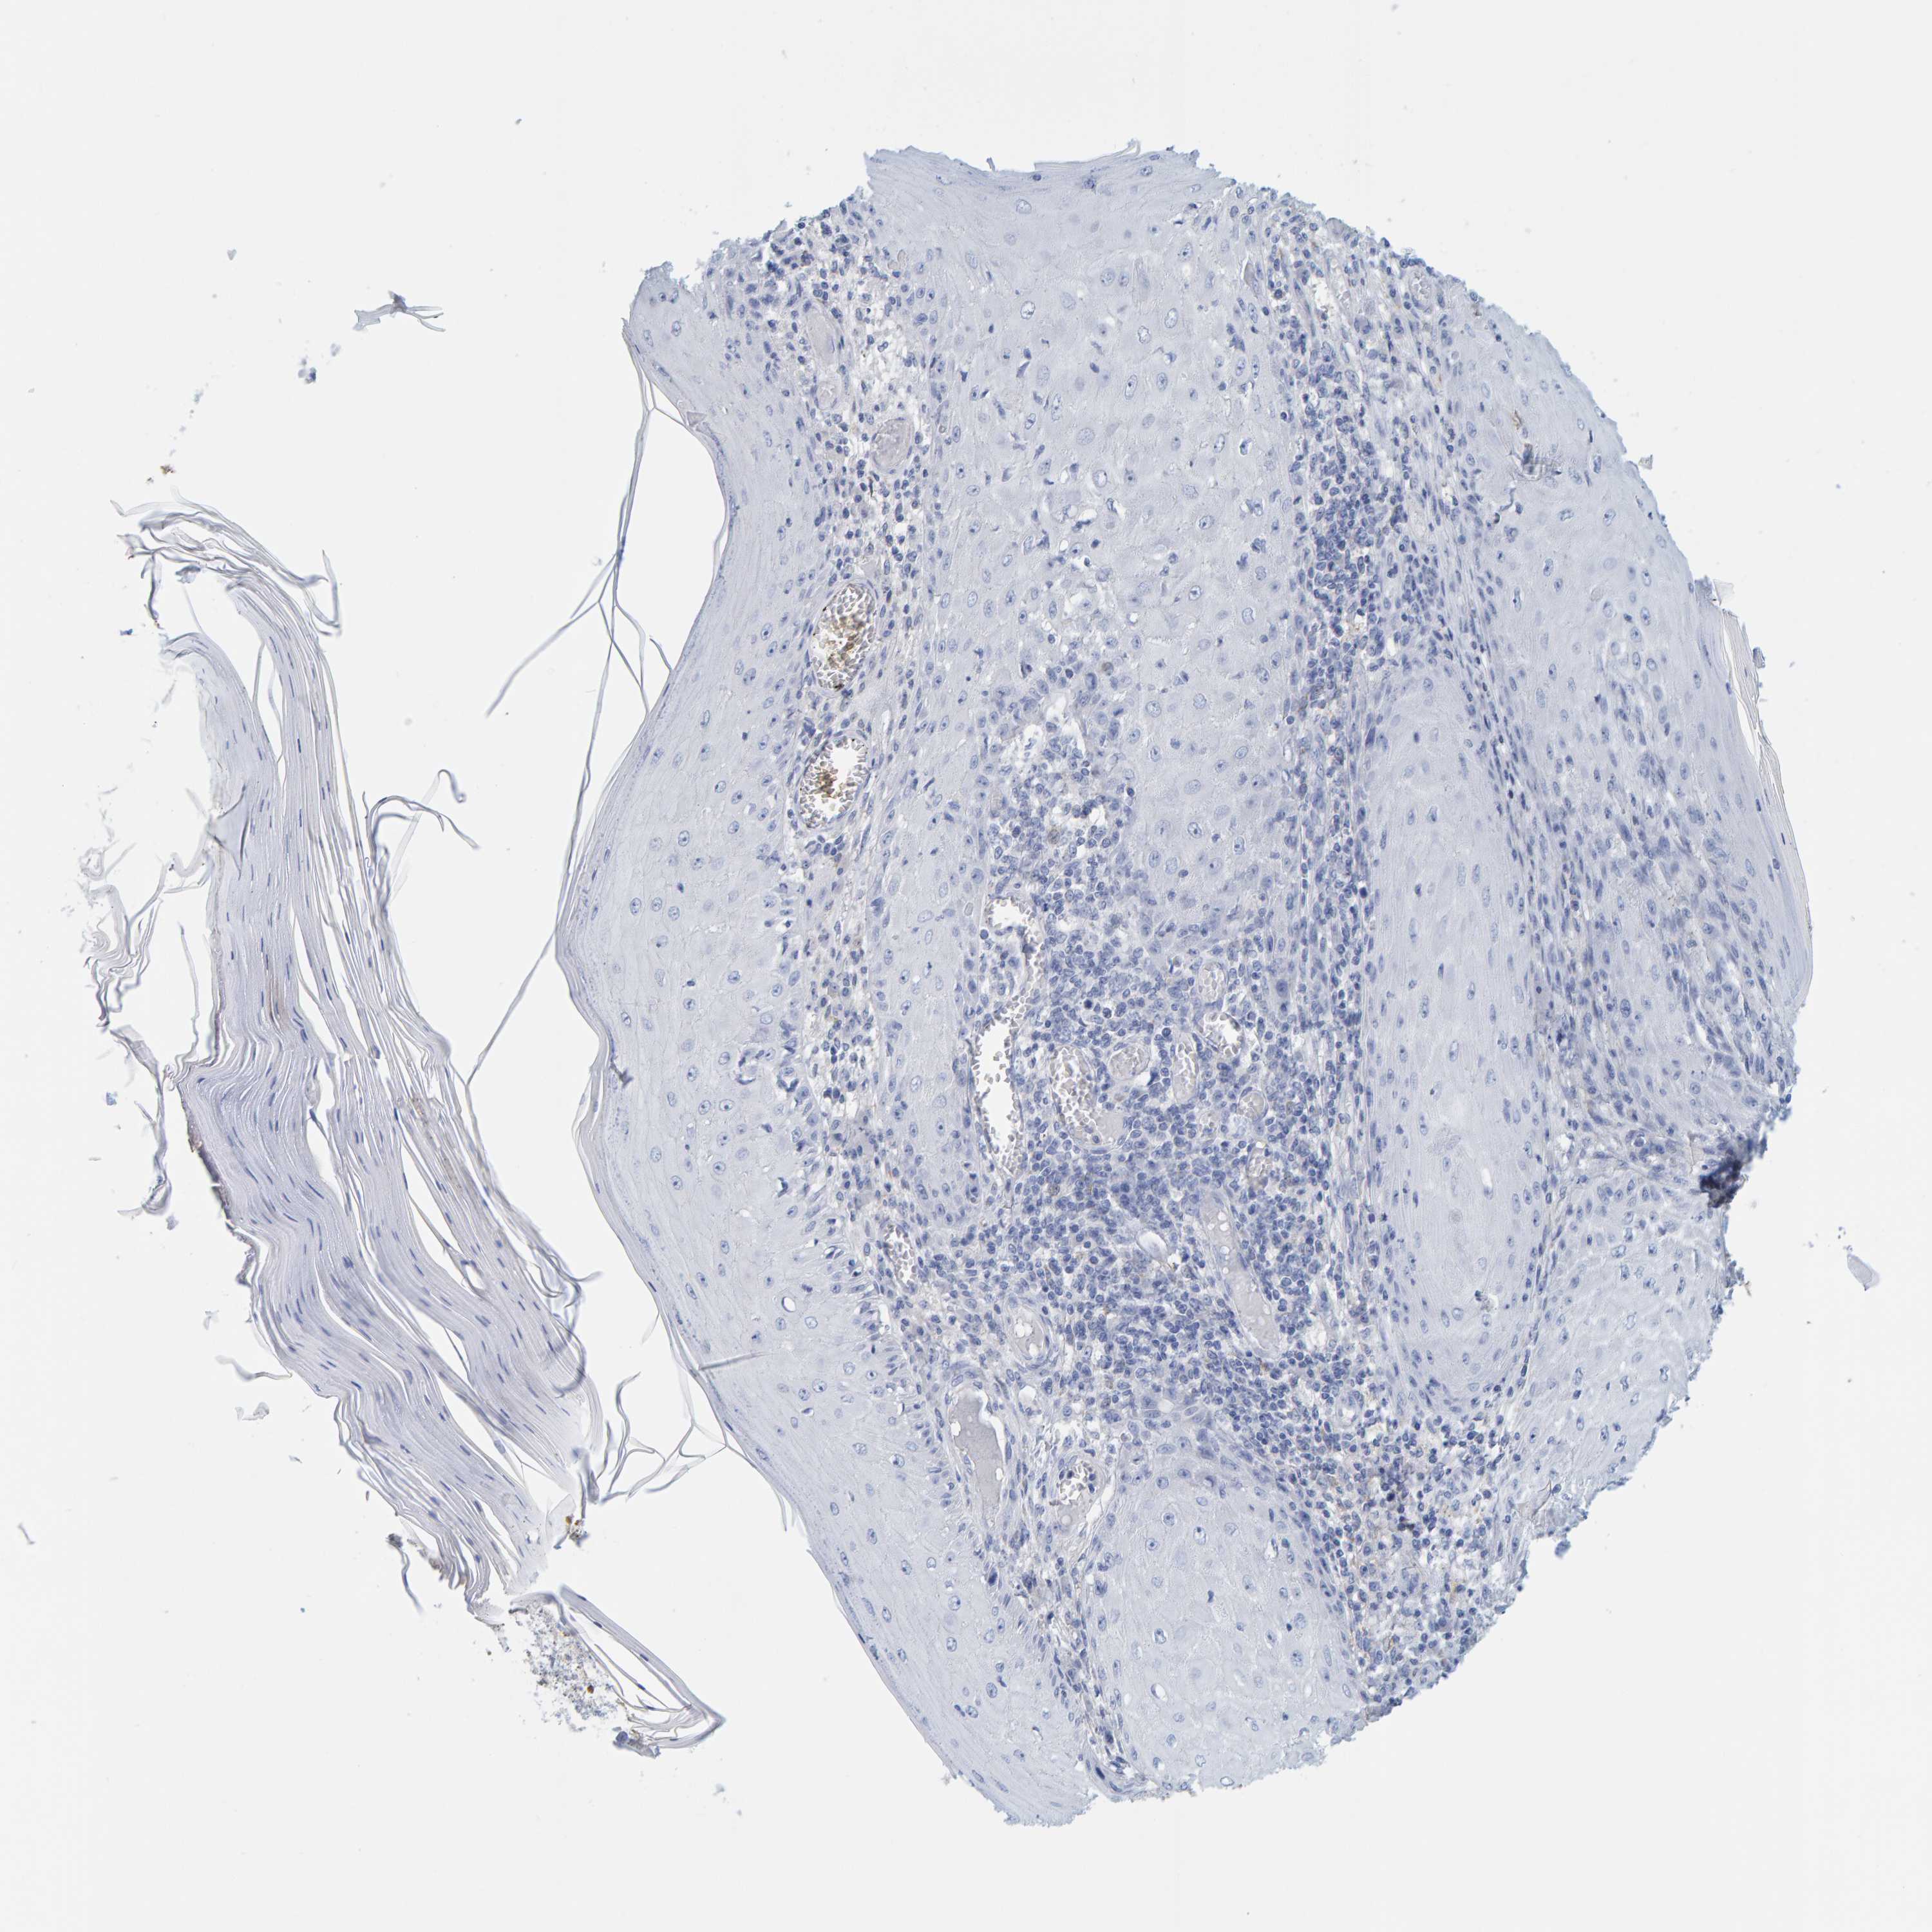

SKIN CANCER - Protein expressioni

A mouse-over function shows sample information and annotation data. Click on an image to view it in a full screen mode. Samples can be filtered based on level of antibody staining by selecting one or several of the following categories: high, medium, low and not detected. The assay and annotation is described here.

Antibody stainingi

Antibody staining in the annotated cell types in the current human tissue is reported as not detected, low, medium, or high, based on conventional immunohistochemistry profiling in selected tissues. This score is based on the combination of the staining intensity and fraction of stained cells.

Each image is clickable and will lead to virtual microscopy that enables deeper exploration of all samples and also displays staining intensity scores, fraction scores and subcellular localization as well as patient and tissue information for each sample.

Antibody HPA054269

Basal cell carcinoma

Squamous cell carcinoma, NOS